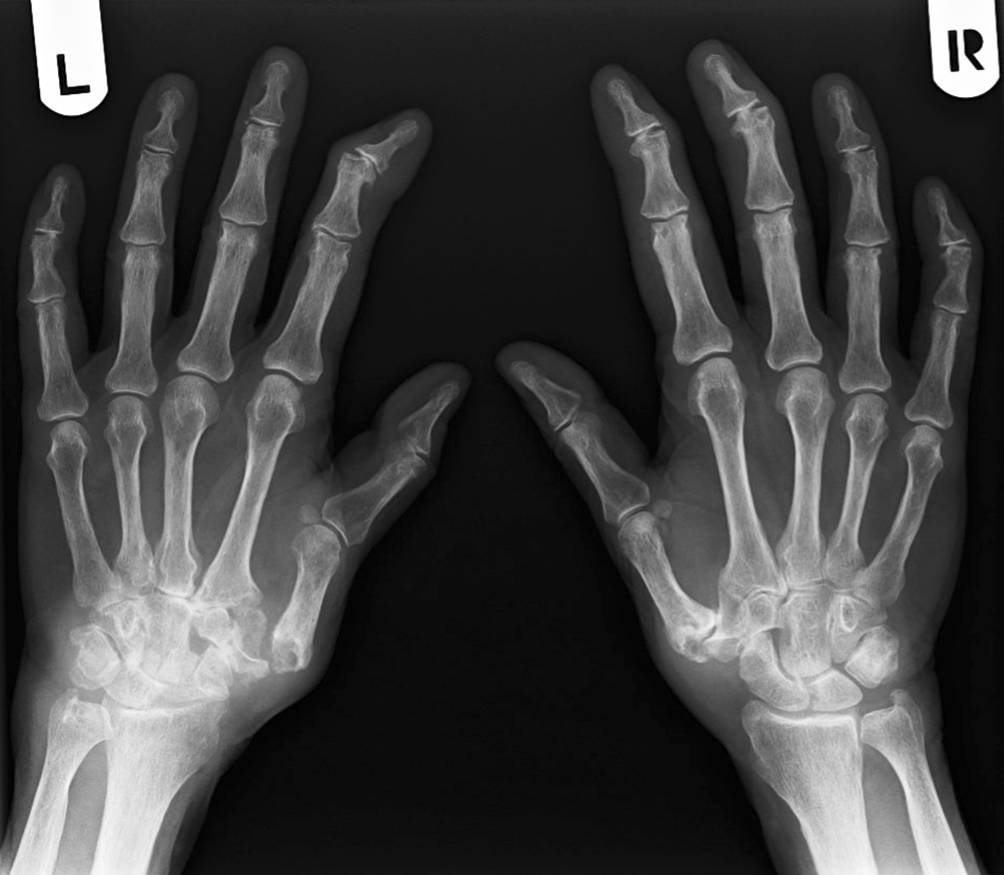

Nativradiologisch war im Bereich der Hände ein Mischbild aus erosiver Polyarthritis (Stadium IV nach Larsen) sowie Heberden- und Bouchard-Arthrosen beidseits sichtbar (Abb. 1). Zusätzlich fanden sich mutilierende Veränderungen der Handgelenke beidseits. Eine Magnetresonanztomographie der Halswirbelsäule zeigte eine aktive Arthritis im Kiefergelenk rechts und im Atlantodentalgelenk.

Abb. 1

Mischbild aus erosiver Polyarthritis (Stadium IV nach Larsen) sowie Heberden- und Bouchard-Arthrosen beidseits (Fall 3)